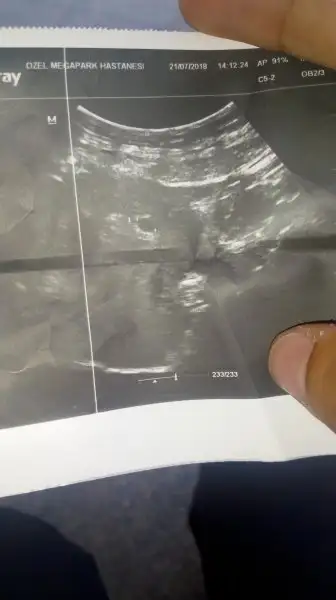

Merhaba hanımlar , henüz yeni uyeyim , biraz riski ve stresli bir hamilelik yaşıyorum . Öncelikle konuya en başından başlamak isterim , sizlerde bilgilerinizi paylasirsaniz bir nebze sayenizde rahatlarim ben en son 21 Mayıs'ta toplam üç gün süren regl oldum , haziran ayı boyunca hiç regl olmadım , temmuz 7 de suphelendim ve çubuk test aldım çift cizgi çıktı , sonrasında ertesi günü hastaneye gittim beta kan testi yaptirdigmda 1037 değeri çıktı . Ama ultrasonda gözükmedi sanırım yeni kaldigim için. Sonrasında 20 temmuzda öğlen kahverengi damlacıklar şeklinde kanama geldi siyah ufak parçalar ve birazda regl şeklinde kokuluydu , sonrasında hemen doktoruma gittim 20 temmuzda beta kan tahlili istedi ve sonuç ikibin li değer çıktı kese yeni oluşmuş şuan için düşük yok ama riskte var dedi bana , ' progestan' hap verdi ve iki adet iğne verdi haftada birer kere vurulcaksin dedi , kanamam devam ediyor ilaç içtiğim halde , fakat şiddetli sancilarim yok. Sanki adet görüyor gibiyim . Ama sürekli doktora gitme isteği oluşuyor korku var açıkçası hem kendi hem bebeğin sağlığı için. Nette okuduğumda ' üstüne görme ' diye bir durumda varmış , acaba o sekildemi suanki durumum bilemiyorum . Belki de geç döllenme sır diyende var , bebek içini temizlermis streslendirdiler diyende var . İlaclarima iğneye devam ediyorum . Ultrason resmimde ensinki şu şekilde , heyecanla yorumlarınızı bekliyorum , şimdiden çok teşekkürler

Canım doktor baktı ve o üstte resmini attığım ultrasonu çekti. Şimdilik gebelik devam ediyor kanda ve ultrasonda normal herşey dedi . Üçüncü gebeligim bu , hem sürpriz oldu , hemde dediğiniz gibi geç döllenme diyen var , doktorum bana üç hafta sonraya randevunu al henüz kese izin içi oluşmamış oluşma evresinde dedi ,üç hafta sonra içi oluşur ve bebeğin kalp sesini duyarız dedi . Beş gundur kanamam var , yoğun değil damla damla geliyor bulantı ateşlenme sancı felan yok. Normal adet görüyor gibiyim . Anlamadım .

Çarşamba günü gittim doktora bana 5+1 günlük gebesiniz ama kesenin içi boş hala oluşmamış dedi kanamam hala devam ediyor , yüksek ihtimalle düşük dedi , ve bir hafta bekleyin kanamaniz artarsa gelin yoksa 6. Haftaya kdr bekleyelim düşmüşse kese , kürtaja alcaz dedi yani gebeligim sonlandi. Rabbimin takdiri. Moral olarak bitmiş durumdayım . Çok zormuş gerçekten . Okurken nasıl etkilenip üzülüyorsun insanlara . Ama başına geldi , rabbim kimselere yasatmasin . Ama dediğim gibi rabbimin takdiri. Pazartesi günü yine gidicem . Eğer kese kendisi dusmemisse kürtaja alcaklar